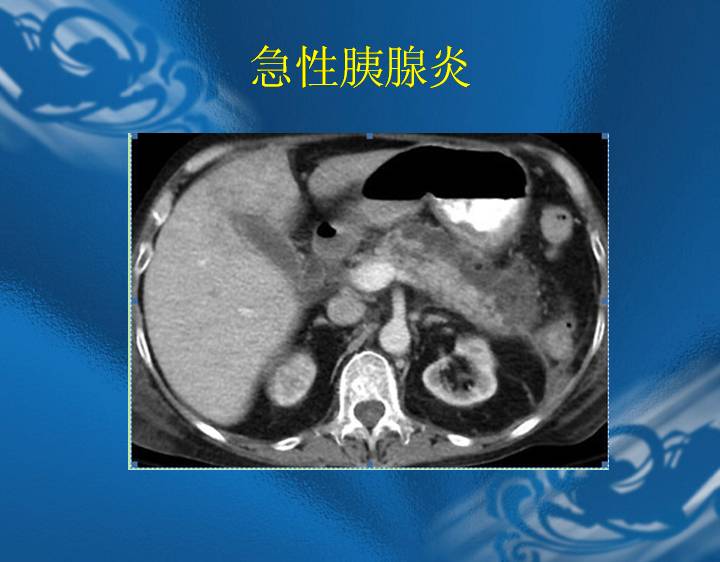

执业医师资格考试“实践技能”影像学辅导资料